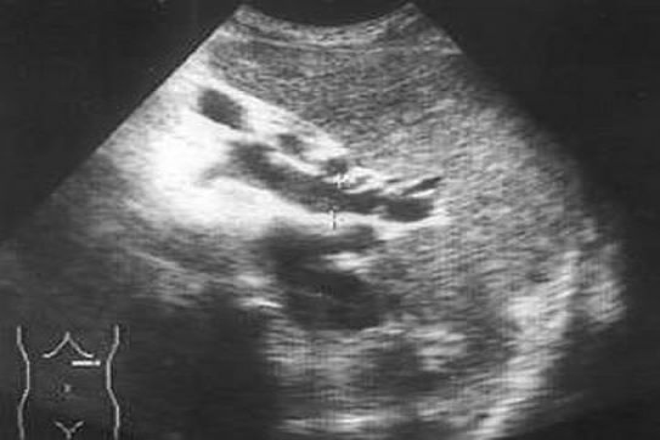

Desafortunadamente en la práctica clínica, he encontrado a menudo pacientes con tumoraciones ováricas asintomáticas que, al acudir a consulta, presentan molestias vagas, principalmente gastrointestinales. Estas suelen diagnosticarse erróneamente como colitis, sin una investigación exhaustiva para sospechar el cáncer de ovario. Es crucial conocer los factores de riesgo y la población